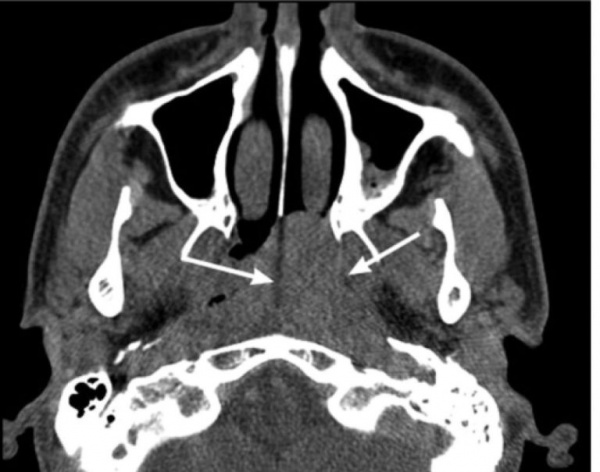

(б) КТ пациента с юношеской ангиофибромой. (в) МРТ пациента с юношеской ангиофибромой.

В первую очередь требуется выполнение КТ с контрастом, что дает возможность определить степень костной деструкции. МРТ является дополнительным методом, позволяющим оценить мягкотканные характеристики опухоли. Диагноз ставится на основании анамнеза, клинических данных и методов визуализации.

- Томография. С целью определения размеров, границ распространения и стадии ЮАН выполняется МСКТ лицевого черепа. На томограммах четко визуализируется мягкотканное образование, расположенное в крыловидно-небной ямке, вызывающее смещение и разрушение костных стенок. При интракраниальном росте осуществляется МРТ головного мозга с контрастом.

Достаточно характерны радиологические признаки опухоли. На КТ определяется смещение задней стенки верхнечелюстной пазухи кпереди, которое называют признаком Holman-Miller. Также характерно расширение верхней глазничной щели, которое является достаточно специфичным для юношеской ангиофибромы. КТ идеально подходит для определения точной локализации и степени распространения опухоли. При прорастании опухоли в полость черепа необходимо выполнить МРТ.